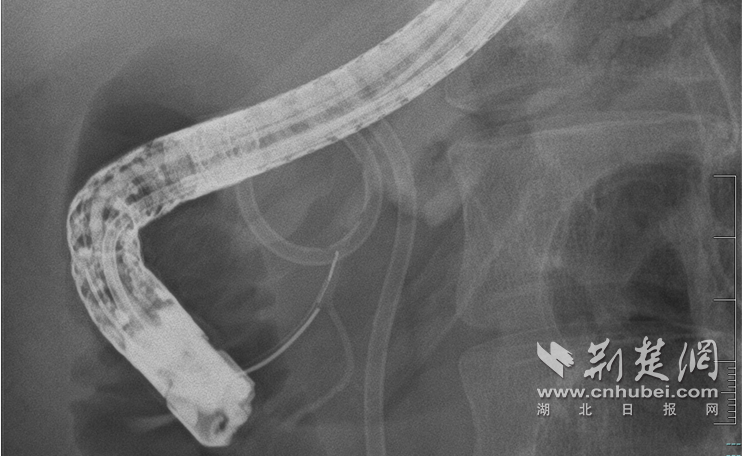

图为内镜下微创修复断裂的胰管

面对这一难题,大家决定迎难而上,在内镜下微创修复断裂的胰管。10月30日,手术术中造影清晰地显示了病情的复杂程度:胰头部胰管扭曲,胰管在颈部完全中断,形成一个直径约2厘米的囊腔,远端的胰体尾部胰管因堵塞而显著扩张。

技术的难点在于空间定位。在医疗团队成员的紧密配合下,覃华和雒真龙副主任医师在X光引导下,将导丝小心翼翼地通过囊腔,精准找到远端胰管细如发丝的断端开口,实现了断裂管道的“胜利会师”!随后,专家们顺利置入支架,为他重建了胰液引流通道。